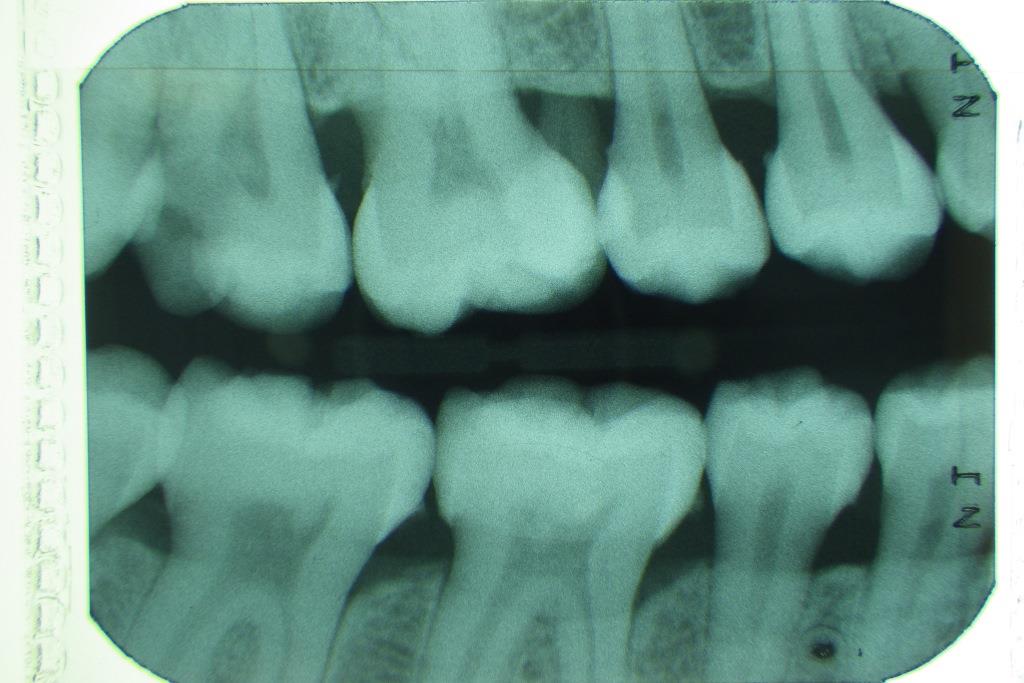

e-bissfluegel-rechts Veröffentlicht 6. Januar 2017 am 1024 × 683 in Neupatientin mit Sammlung seltener Befunde